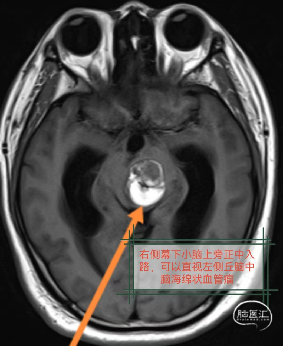

神经内镜下经右侧旁正中幕下小脑上入路(PM-SCITA)切除左侧丘脑中脑海绵状血管瘤;从右侧进入可以直视左侧的病变。

从右侧显露左侧丘脑及中脑病变直视下手术非常重要;